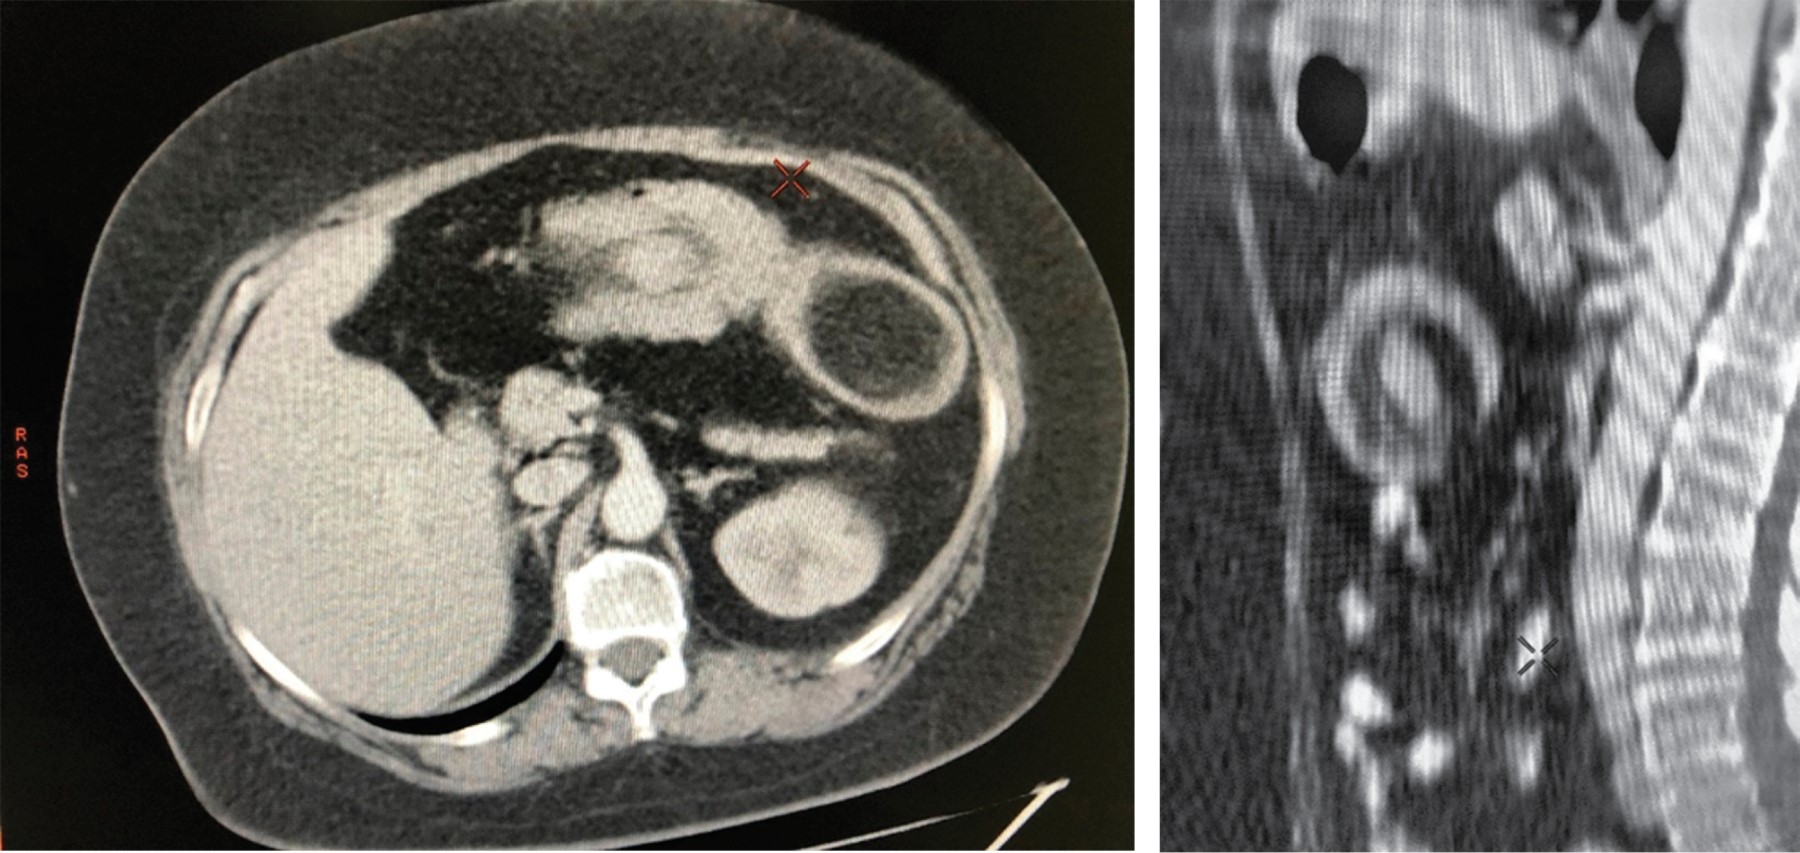

La tomografía contrastada (TC) de abdomen mostró a nivel de colon transverso una tumoración bien delimitada, de 4.6 × 7.7 × 6.5 cm, con densidad de 115 unidades Hounsfield (escala cuantitativa utilizada en los estudios de TC para describir los diferentes niveles de radiodensidad de los tejidos), que se invaginaba en el lumen del mismo colon transverso y con discreto proceso inflamatorio de la grasa perilesional (Figura 1).

La tomografía de abdomen (con contraste oral e intravenoso [IV]) es el método más sensible (71 al 87%) y específico (cerca del 100%), porque se observa la masa con densidad de grasa (80-120 unidades Hounsfield) y el signo clásico de tiro al blanco o masa en forma de salchicha.10,11 El ultrasonido también nos puede ofrecer datos que orienten el diagnóstico, sin embargo, al ser operador dependiente su sensibilidad y especificidad varía.12